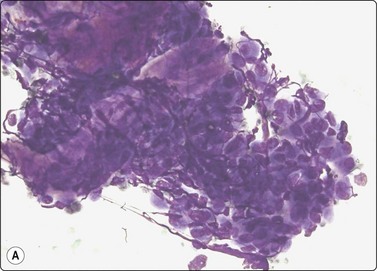

Chromophobe renal cell carcinoma

Criteria for diagnosis

Moderately to highly cellular smears,

Small, loosely cohesive monolayered sheets and single cells with intact cytoplasm,

Mixture of large cells with abundant, pale, flocculent cytoplasm and smaller cells with dense cytoplasm, flocculent,

Thick cell membrane, cytoplasm dense peripherally, pale centrally (halo),

Nuclear grade usually 2, anisokaryosis, binucleation common, small nucleoli,

No stromal material, no necrosis,

CK7+, vimentin−, RCC antigen variable, CD10−, CD117+.

Five percent of RCCs are of the chromophobe type (Figs 12.19 and 12.20). Smears of chromophobe RCC are cellular, showing both single cells and small sheets. There is a conspicuous variation in the size of the cells. Most cells are large with abundant, vacuolated cytoplasm of a flocculent texture. The cytoplasmic density varies; it is dense at the periphery and pale in the center, like a perinuclear halo. Cell membranes are thick. There are also groups of smaller cells with dense cytoplasm, giving an impression of a dual population. There is moderate anisokaryosis, but the nuclear:cytoplasmic ratio is consistently low. Nuclei are moderately hyperchromatic and nucleoli are small. Nuclear grade is mainly 2. The nuclear membranes have been described as irregular and ‘raisinoid’. Binucleation is a common feature, and small nuclear inclusions occur.76-78

image image

Fig. 12.19 Renal cell carcinoma, chromophobe type

Clustered cells, majority with abundant granular and vacuolated cytoplasm, some much smaller cells; moderate anisokaryosis, some cells with small nucleoli. Cytoplasm condensed peripherally, perinuclear pale area, best seen in Pap (A, MGG; B, Pap, HP).

Fig. 12.20 Renal cell carcinoma, chromophobe type

(A) A dual population of large and smaller cells more obvious in this example (H&E, HP); (B) Corresponding tissue section (H&E, IP).

Renal oncocytoma is the main differential diagnosis in FNB smears. Cells of oncocytoma have dense granular eosinophilic cytoplasm and small bland nuclei of uniform size.79 Immune markers are helpful in this distinction.80,81